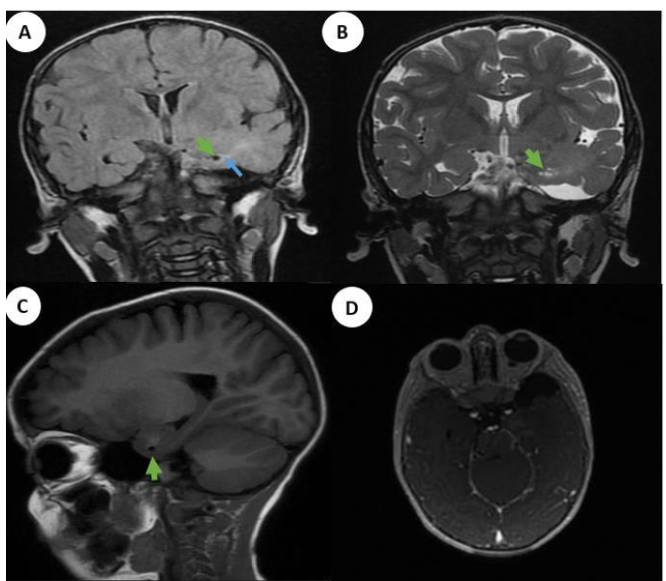

Agenesis of the Corpus Callosum and Neuropsychiatric Manifestations: About a Case Partial Anterior Agenesis and Review of Literature

N Amsiguine, S Choayb, A Lahfidi, F Touarssa, M Fikri, N Elkettani and M Jiddane. 15(6): 33-37.